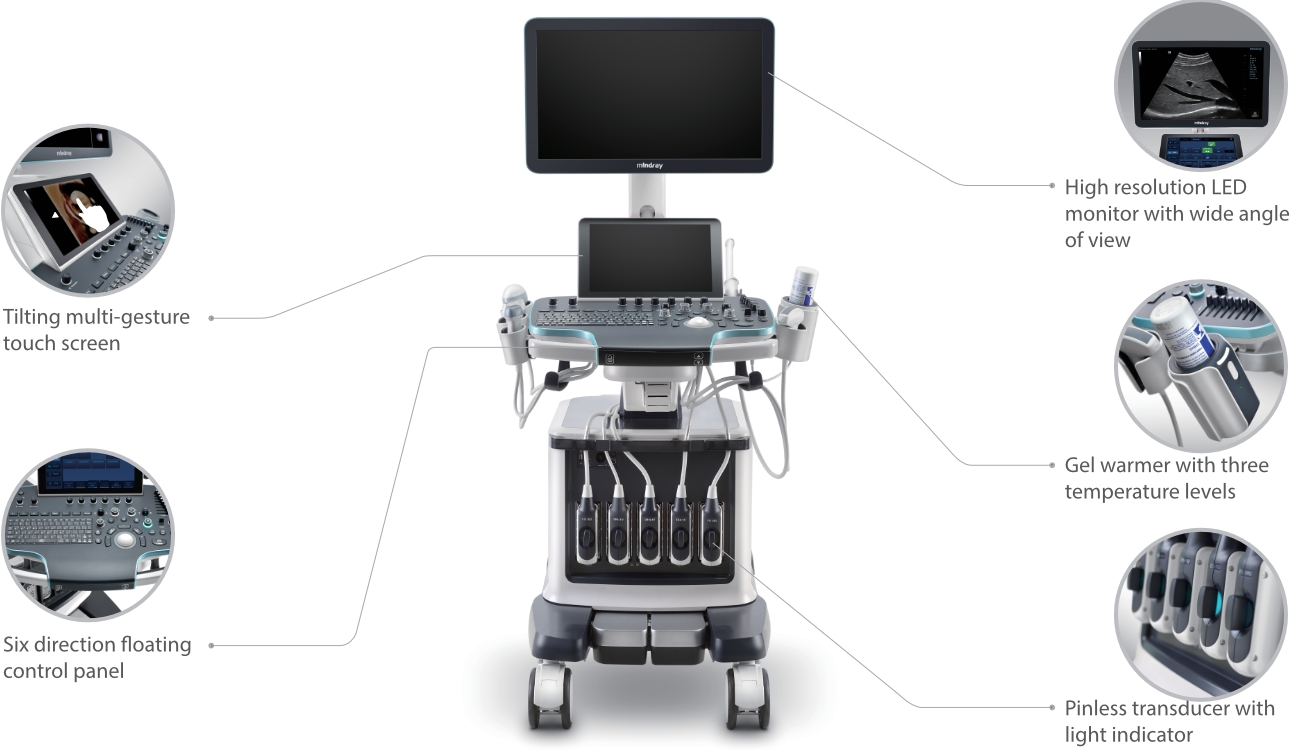

Resona 7

New Waves in Ultrasound Innovation

With Zone Intelligence

Since the company was founded, Mindray has been continuously exploring new ways to improve diagnostic confidence. Powered by the most revolutionary ZONE Sonography? Technology, Resona 7ŌĆÖs new ZST+ platform brings ultrasound image quality to a higher level by zone acquisition and channel data processing.

As well as the premium level image quality, Resona 7 also enhances clinical research capabilities with the revolutionary V Flow for vascular hemodynamic evaluation, and the most intelligent plane acquisition from 3D datasets for fetal CNS diagnosis. Combining the most intuitive gesture-based multi-touch operation and all the essential clinical features, Resona 7 is truly leading new waves in ultrasound innovation.